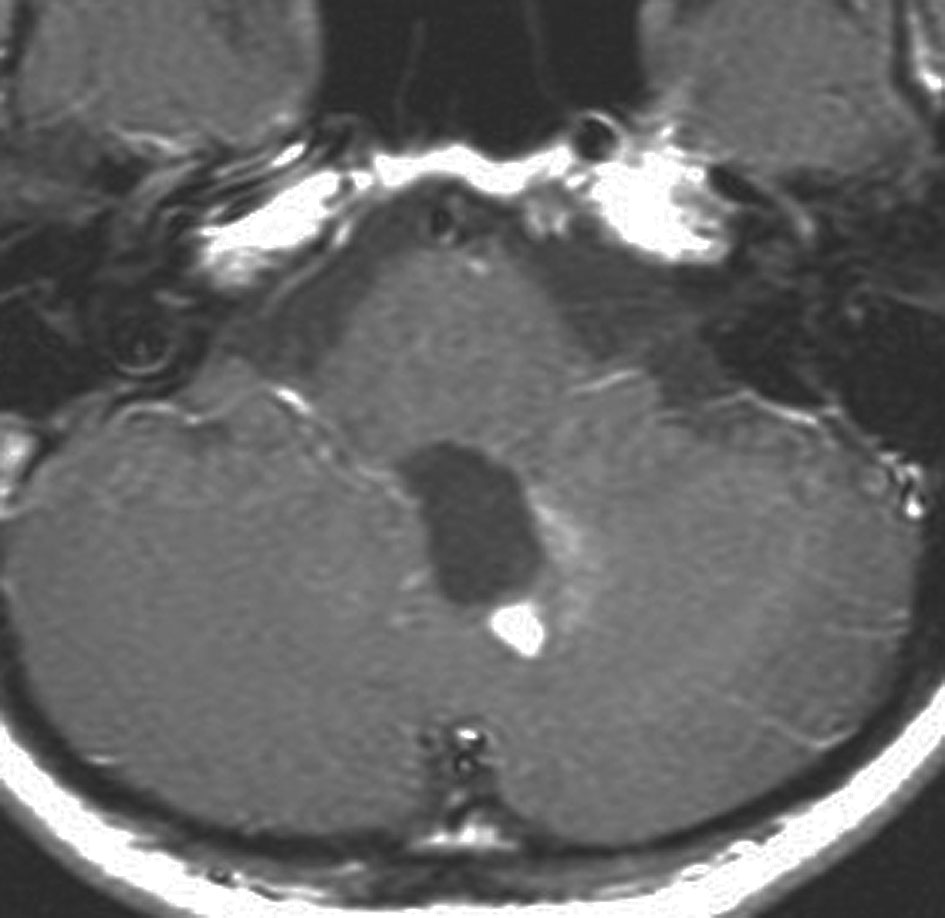

18歳で発症して,60歳まで無治療の大きな視床下部毛様細胞性星細胞腫

hypothalamic pilocytic astrocytoma

1968年 18歳の時に頭痛嘔吐で発症しました。第3脳室腫瘍と閉塞性水頭症の診断だけで,シャント手術を受けました。手術も化学療法も放射線治療もされていません。下の画像は60代で撮影されたものです。この例では,第3脳室内に増大した大きな毛様細胞性星細胞腫が,視床下部下垂体障害を出すことなく,自然経過で増大停止 growth arrest して,カチカチに固まってしまうということを教えてくれます。でも,こんなに都合よく経過観察できる例も珍しいです。

CTでは強い石灰化があります。右のT2強調画像では腫瘍は等信号,視交叉の後ろにあります。内部の低信号は石灰化です。

T1強調画像では等信号,ガドリニウム増強でごく一部がまだらに増強されます。